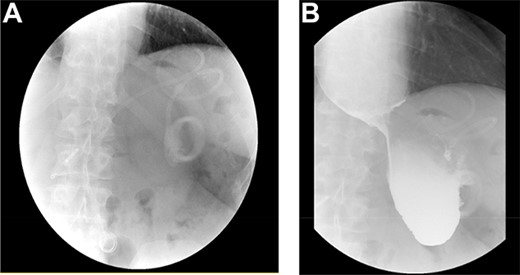

As part of the assessment, computed tomography (CT) coronary angiogram study was performed and it demonstrated a large fluid-filled oesophagus causing partial compression of the left atrium. Barium swallow (Fig. 1A and B), CT chest and abdomen (Fig. 2A and B) and transthoracic echocardiography (TTE) showed a 7.1-cm dilated oesophagus causing left atrial compression and a small hiatal hernia (Fig. 3).

(A) ECHO showing left atrial compression from megaoesophagus during diastole; (B) ECHO showing normal-sized left atrium 3 months after band removal.

Three months after band removal, the patient reported complete resolution of his symptoms. Repeat gastroscopy demonstrated oesophageal mucosal healing and no residual hiatal hernia. TTE showed that left atrium was moderately enlarged (but to a lesser extent compared to previous study) and normal left and right ventricular systolic function and dimensions with estimated left ventricular ejection fraction of 60%. Furthermore, the post-operative Barium swallow study (Fig. 4) demonstrated a 6.7-cm oesophageal dilatation and dysmotility. There was no significant delay in passage of barium into a non-distended stomach. Since band removal his weight had increased by 17 kg (112.8 kg, BMI: 36.4). Further discussions with the patient led to laparoscopic sleeve gastrectomy a month later (Fig. 5).